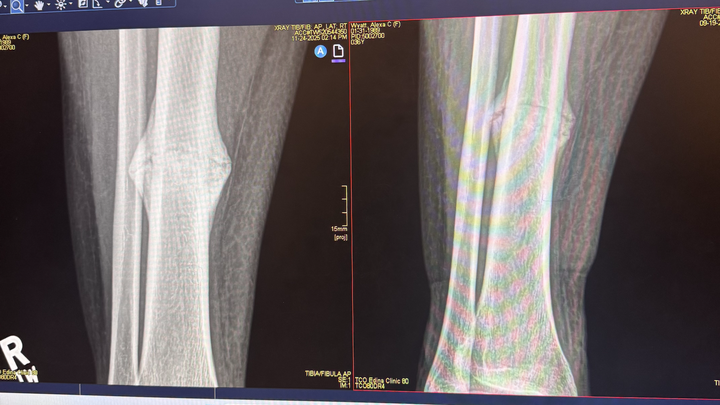

My name is Jessica, and I am Alexa’s partner. In July, Alexa suffered a tibial fracture that has significantly affected her mobility and ability to work. Over the past five months, she has pursued every recommended non-surgical treatment option in hopes of healing naturally. Unfortunately, medical evaluation has now confirmed that surgery is necessary in order for her to properly heal.